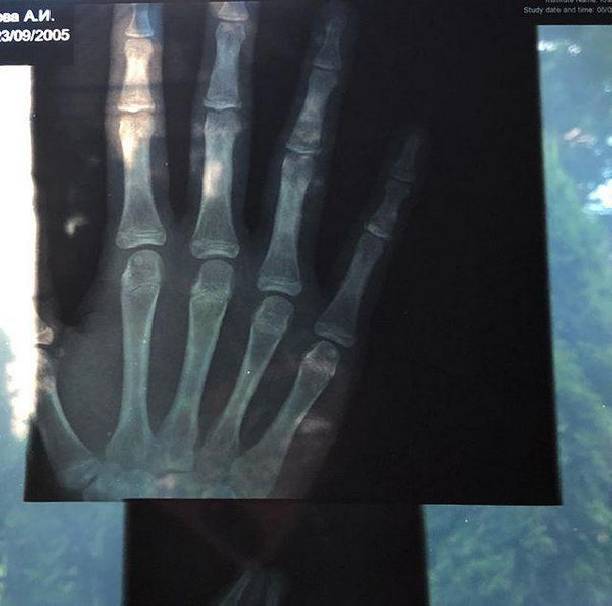

Девушка увлекается конным спортом и много времени уделяет своему хобби. На днях же Ариадна опубликовала в своем микроблоге рентгеновский снимок, сообщив о том, что она сломала руку.

«Конный спорт — это серьезная вещь. К которой нужно подходить с ответственностью», — поведала девушка. — «К которой нужно подходить с ответственностью. Ведь спорт — это сложная и упорная работа».